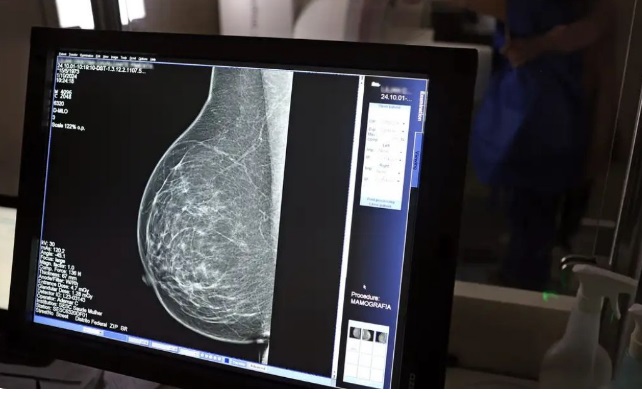

O efeito vai além do cuidado individual. Quando exames são feitos com regularidade, doenças como câncer de mama, próstata e colo do útero podem ser identificadas mais cedo, o que aumenta as chances de tratamento e reduz afastamentos longos.